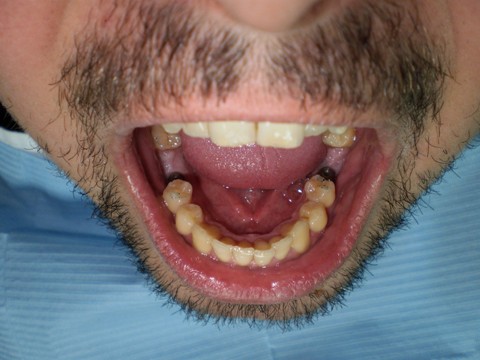

Ejemplo Implantes